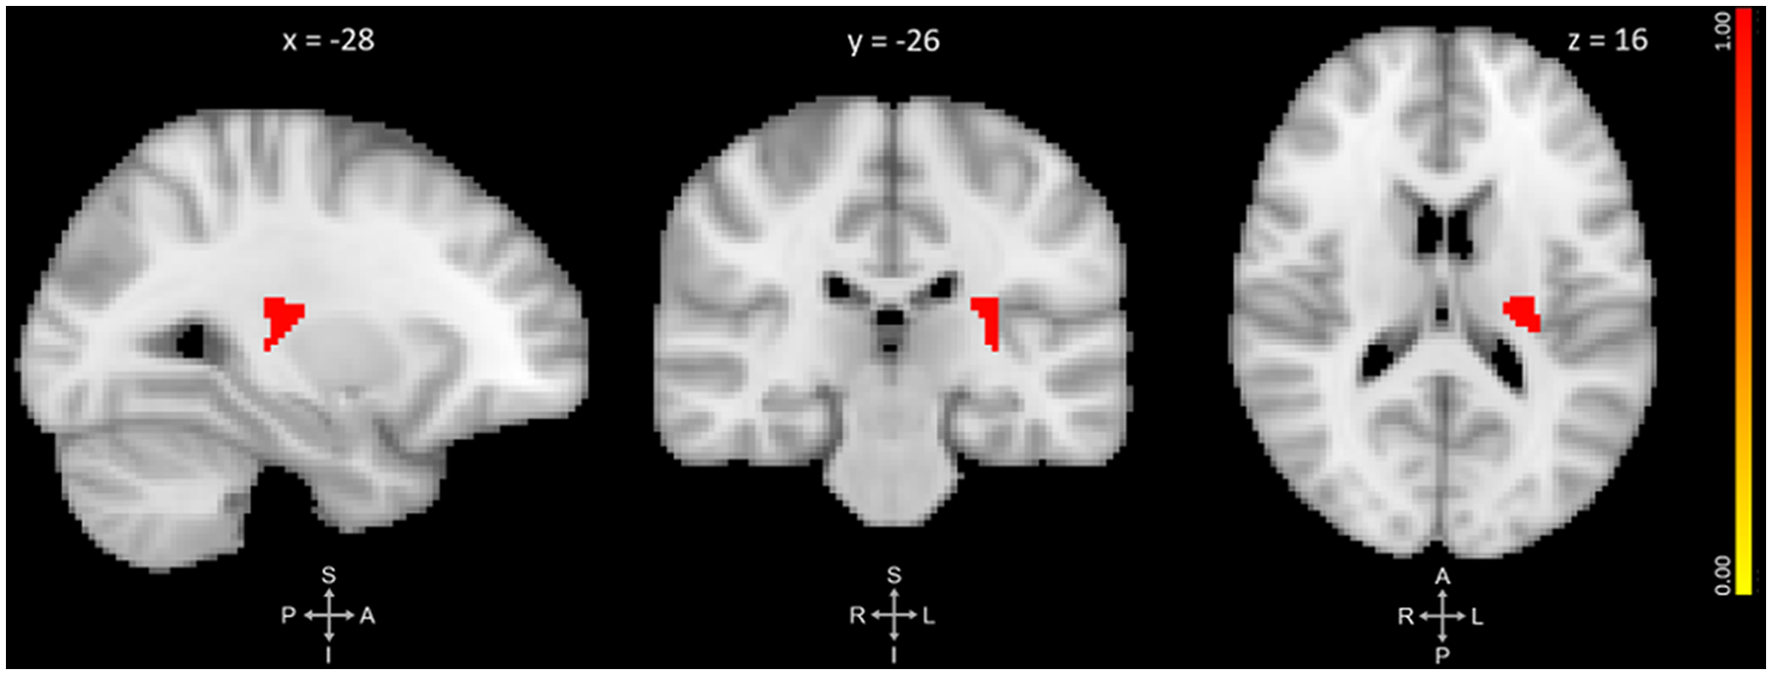

The primary VBM analysis identified one cluster that showed significant GMV reduction between pre- and post-training. The cluster extended medially into the left thalamus and left putamen with its peak in the left posterior insula (p = 0.019, d = 0.47). No regions showed significant GMV increase. See Figure 1 and Table 2 for results.

Figure 1. Three-plane view of the region showing significant gray matter (GM) volume decrease after meditation training. The cluster showed the most significant change at the left posterior insula [PI; p ≤ 0.025, threshold-free cluster enhancement (TFCE)-corrected for family-wise errors]. The cluster also overlapped with the left thalamus and left putamen. The cluster is overlaid over the MNI 2 mm brain template, and coordinates are in MNI standard space. The right-side color bar corresponds to the cluster’s significance (1-p).